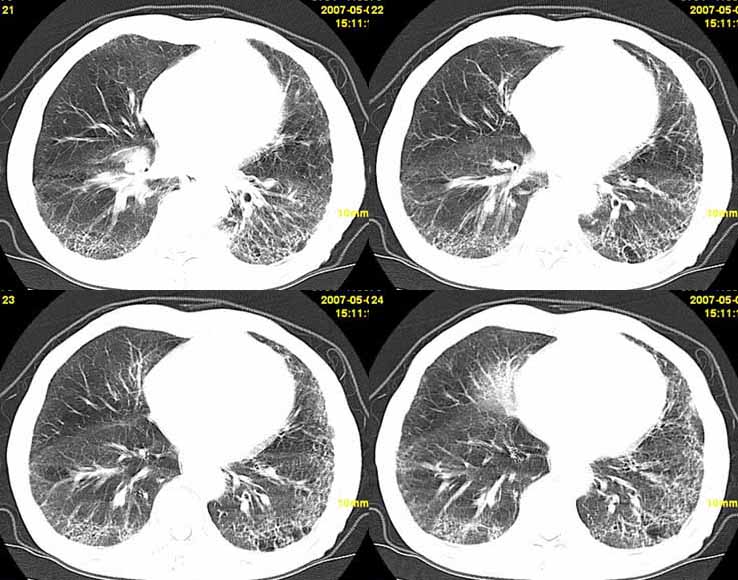

以下是引用小初学者在2007-5-12 11:09:00的发言:[br][br]双肺弥漫性质纤维化(考虑矽肺所致),并发左肺下叶背段周围性肺癌纵隔淋巴转移。

以下是引用zhangzhongshou在2007-5-12 12:09:00的发言:[br]1、左下叶背段周围型肺癌左肺门及纵隔淋巴结转移可能性大。[br]2、弥漫性肺气肿(双侧)。[br]3、双肺间质纤维化。

以下是引用老爱克斯新网客在2007-5-12 12:54:00的发言:[br]1周围型肺癌纵隔肺门淋巴结转移,2肺间质纤维化,